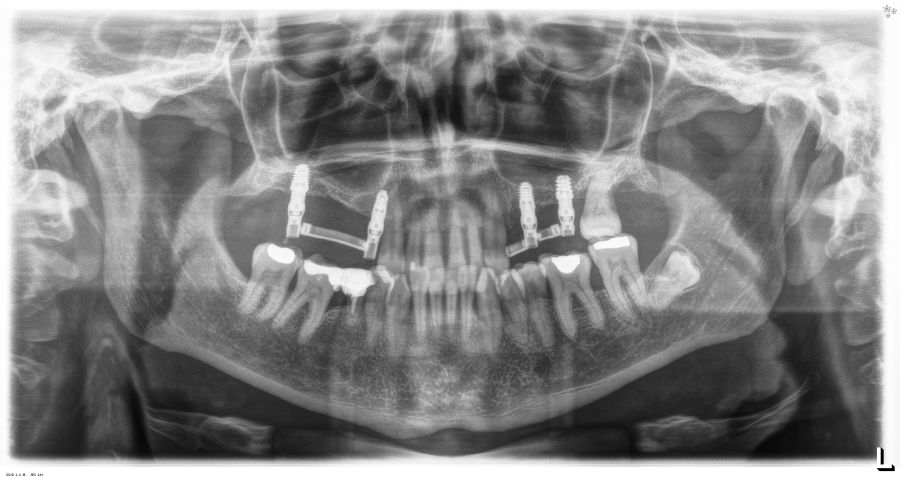

Presentamos el caso de una paciente femenina de 56 años de edad que acude a la consulta demandando un tratamiento con implantes dentales para reponer los dientes ausentes en ambos sectores posteriores maxilares. En ambos cuadrantes superiores, los molares se perdieron hace varios años. La paciente no se ha realizado la reposición de los mismos hasta ahora, ya que en otros centros consultados la propuesta terapéutica fue la de realizar injertos y regeneración ósea para poder ganar volumen óseo suficiente antes de colocar los implantes. La paciente busca otras alternativas menos invasivas y por ello acude a la visita. En las imágenes intraorales se observa la falta de los molares en los sectores posteriores maxilares con excepción del 27, que actualmente tiene un compromiso periodontal importante (Figuras 1-4). El resto de dientes también se encuentran afectados por una enfermedad periodontal avanzada con pérdida ósea horizontal (Figura 5).

Transcurridos 6 meses desde la carga inicial progresiva, se puede elaborar la prótesis definitiva, trasladando los parámetros de la prótesis provisional (Figura 27). La paciente continúa en seguimiento durante un año, realizándose radiografías de control para el monitoreo del hueso crestal, sin encontrarse pérdida ósea asociada en ninguno de los implantes (Figuras 28-29).